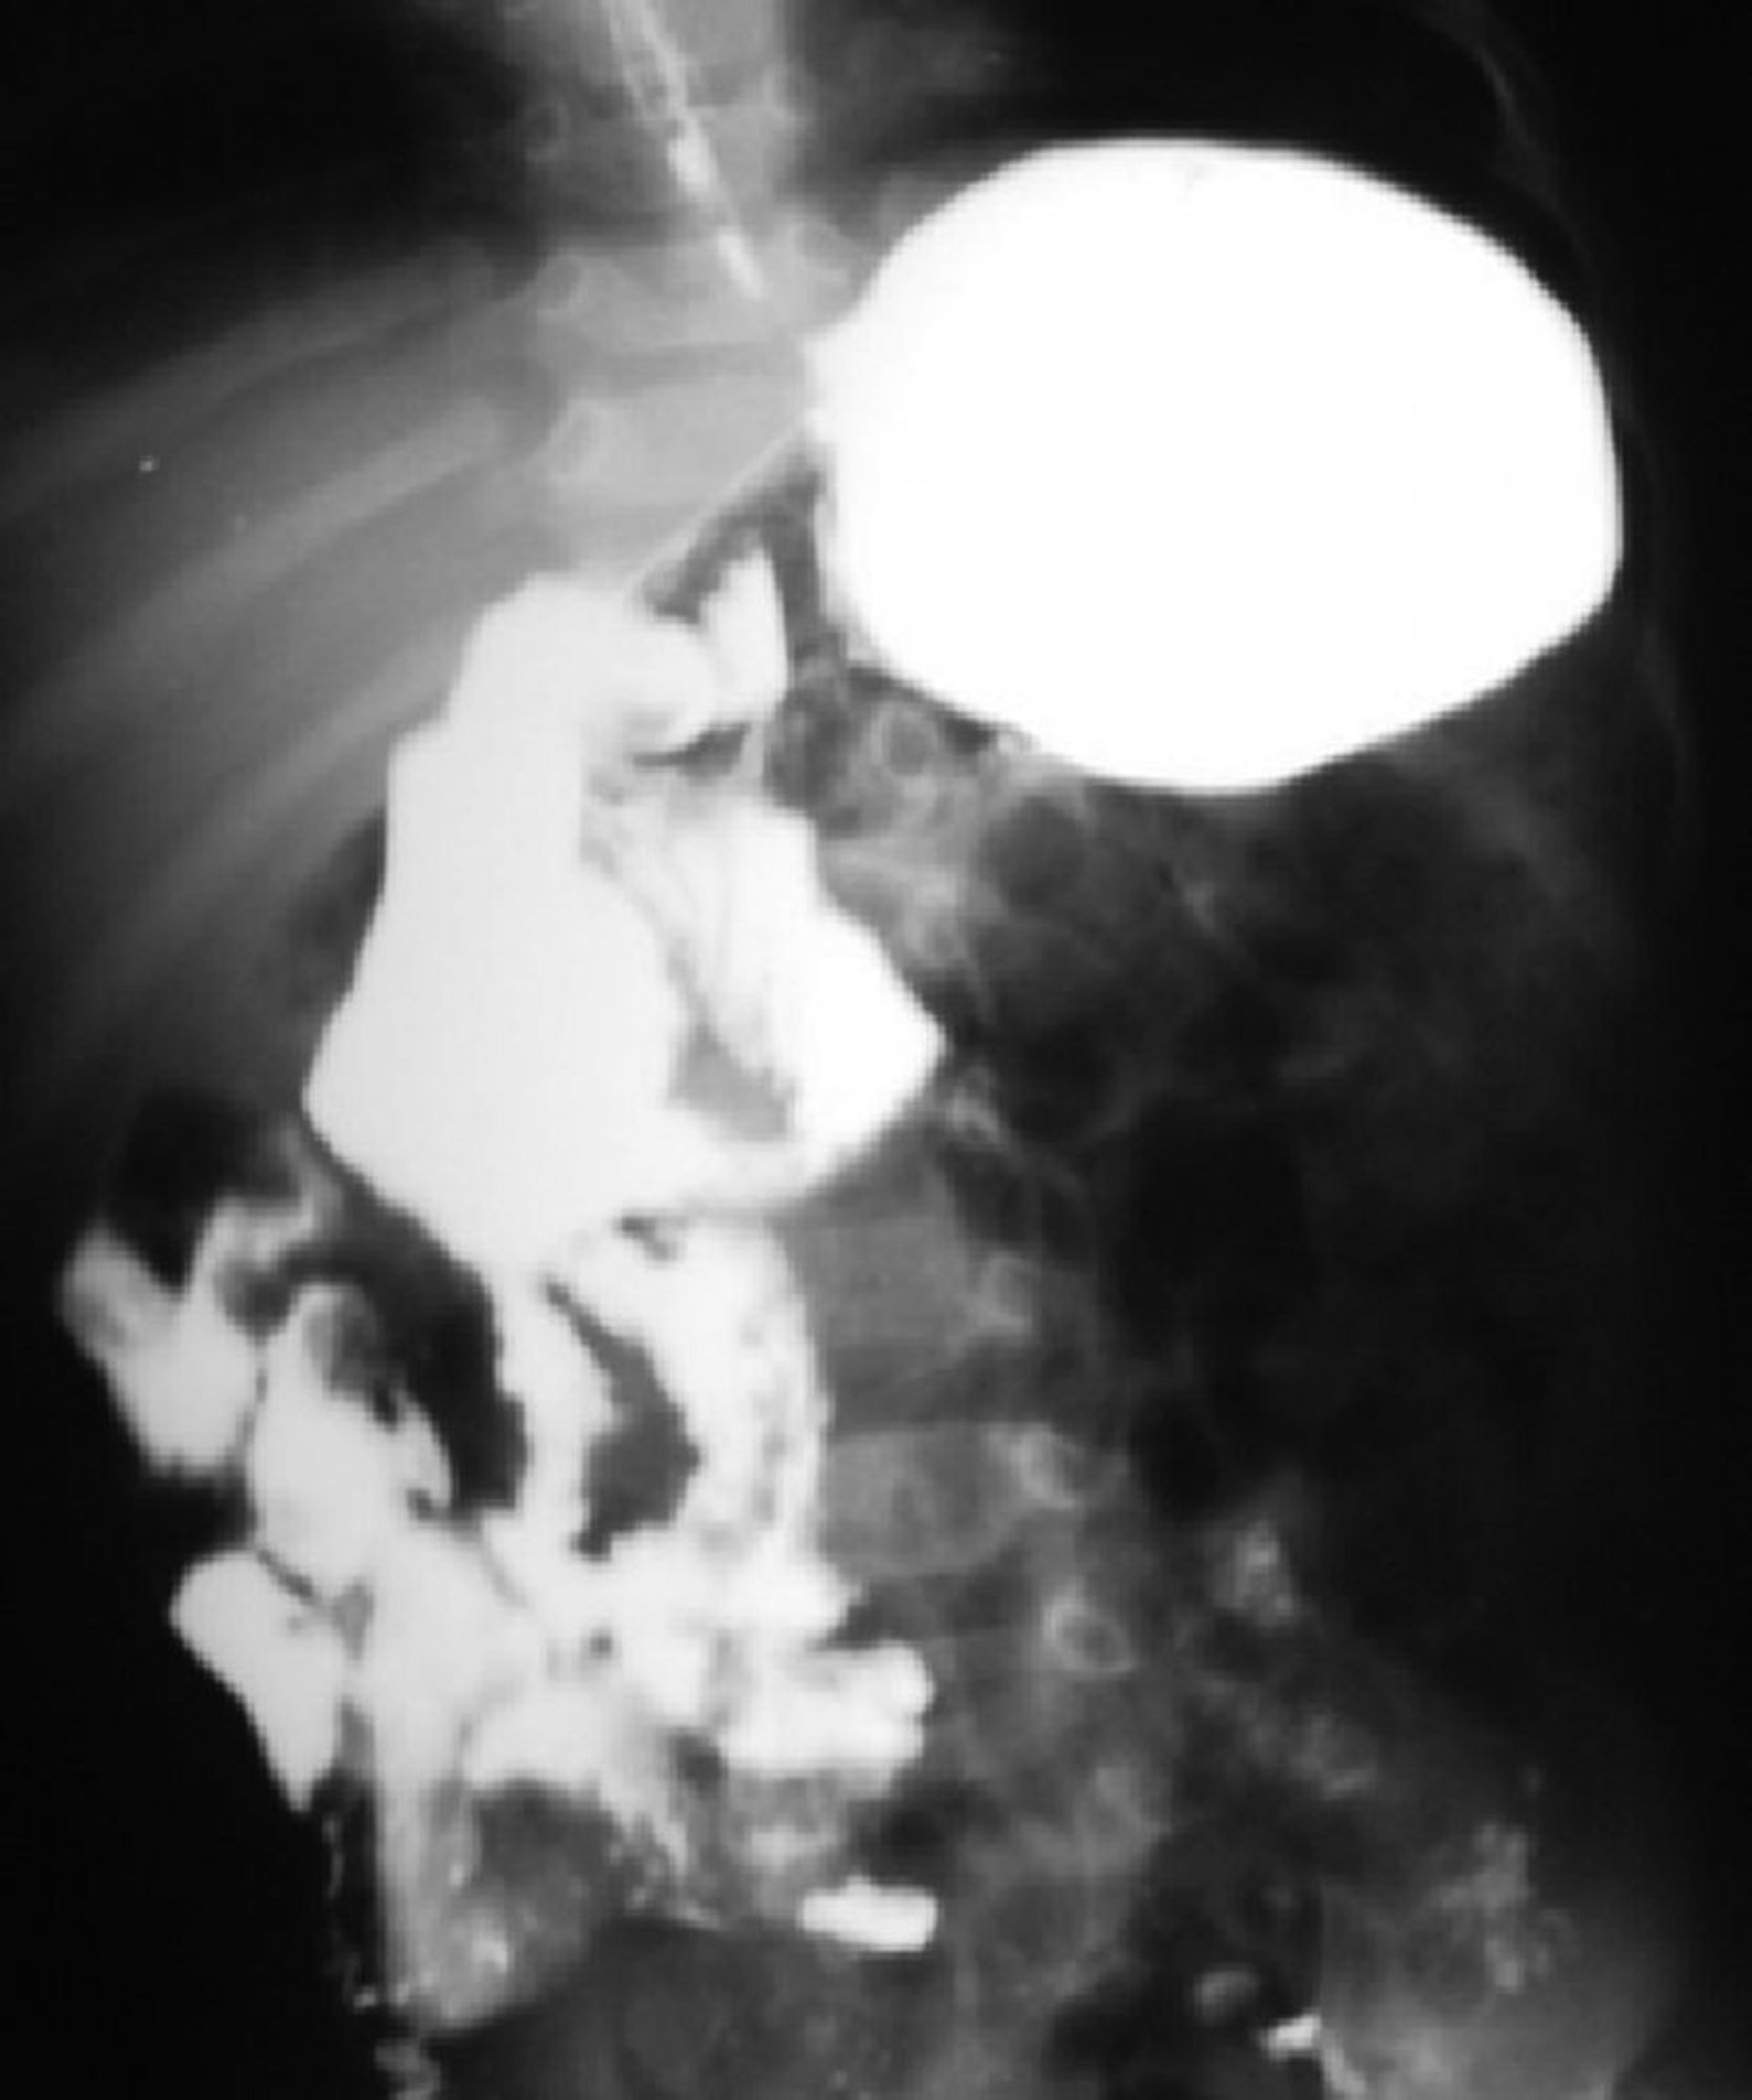

This barium study shows malrotation of the bowel. The duodenojejunal junction is on the right side of the spine, and most of the small intestine is on the right side.